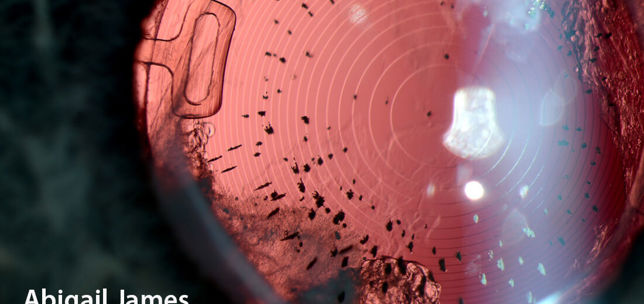

The ANTerior Segment Imaging Competition from Eye News and Keeler promotes and celebrates the work of slit-lamp imaging, culminating in cash prizes and exposure for its winners.

After a successful run in 2024, the ANTS Imaging Competition returned this year with another overwhelming response and our judges were thrilled to have so many amazing images to choose from. We would like to offer a huge congratulations to our winners, honorary mentions, and shortlisted entries, all of which can be seen below. So, without further ado, here some of the best ophthalmic imagers, optometrists and allied professionals in the UK right now: